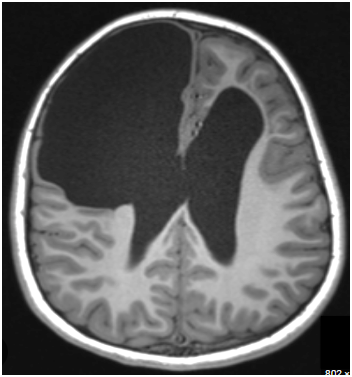

Porencephalic cyst